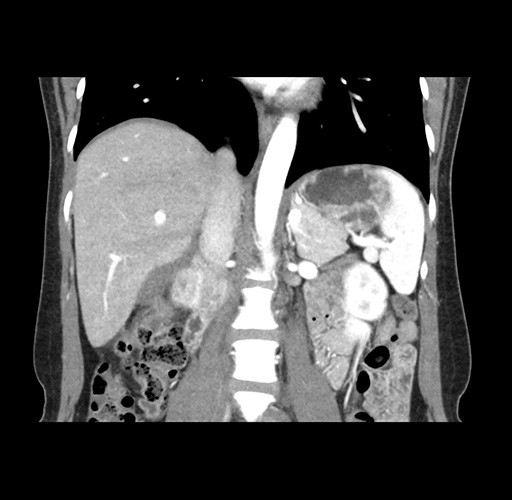

Imaging Analysis

Look through the patient's CT scan to identify any areas of concern for the necessary procedure.

Based on your CT findings, which issue(s) would give reason for "planned slowing down moment(s)" in this case?

Considering a standard left lateral sectionectomy procedure, what step(s) of the operation would you do differently in this case ?